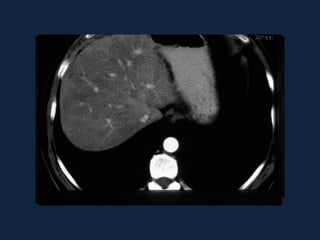

CONGESTÃO HEPÁTICA

• Insuficiência cardíaca levando a

estase na VCI e dificuldade de

drenagem das veias hepáticas.

• Hepatomegalia, dilatação da VCI

e das veias hepáticas.

• Aspecto “em mosaico” do

parênquima hepático que se

homogeniza tardiamente.

• Ascite.

• Halo periportal.